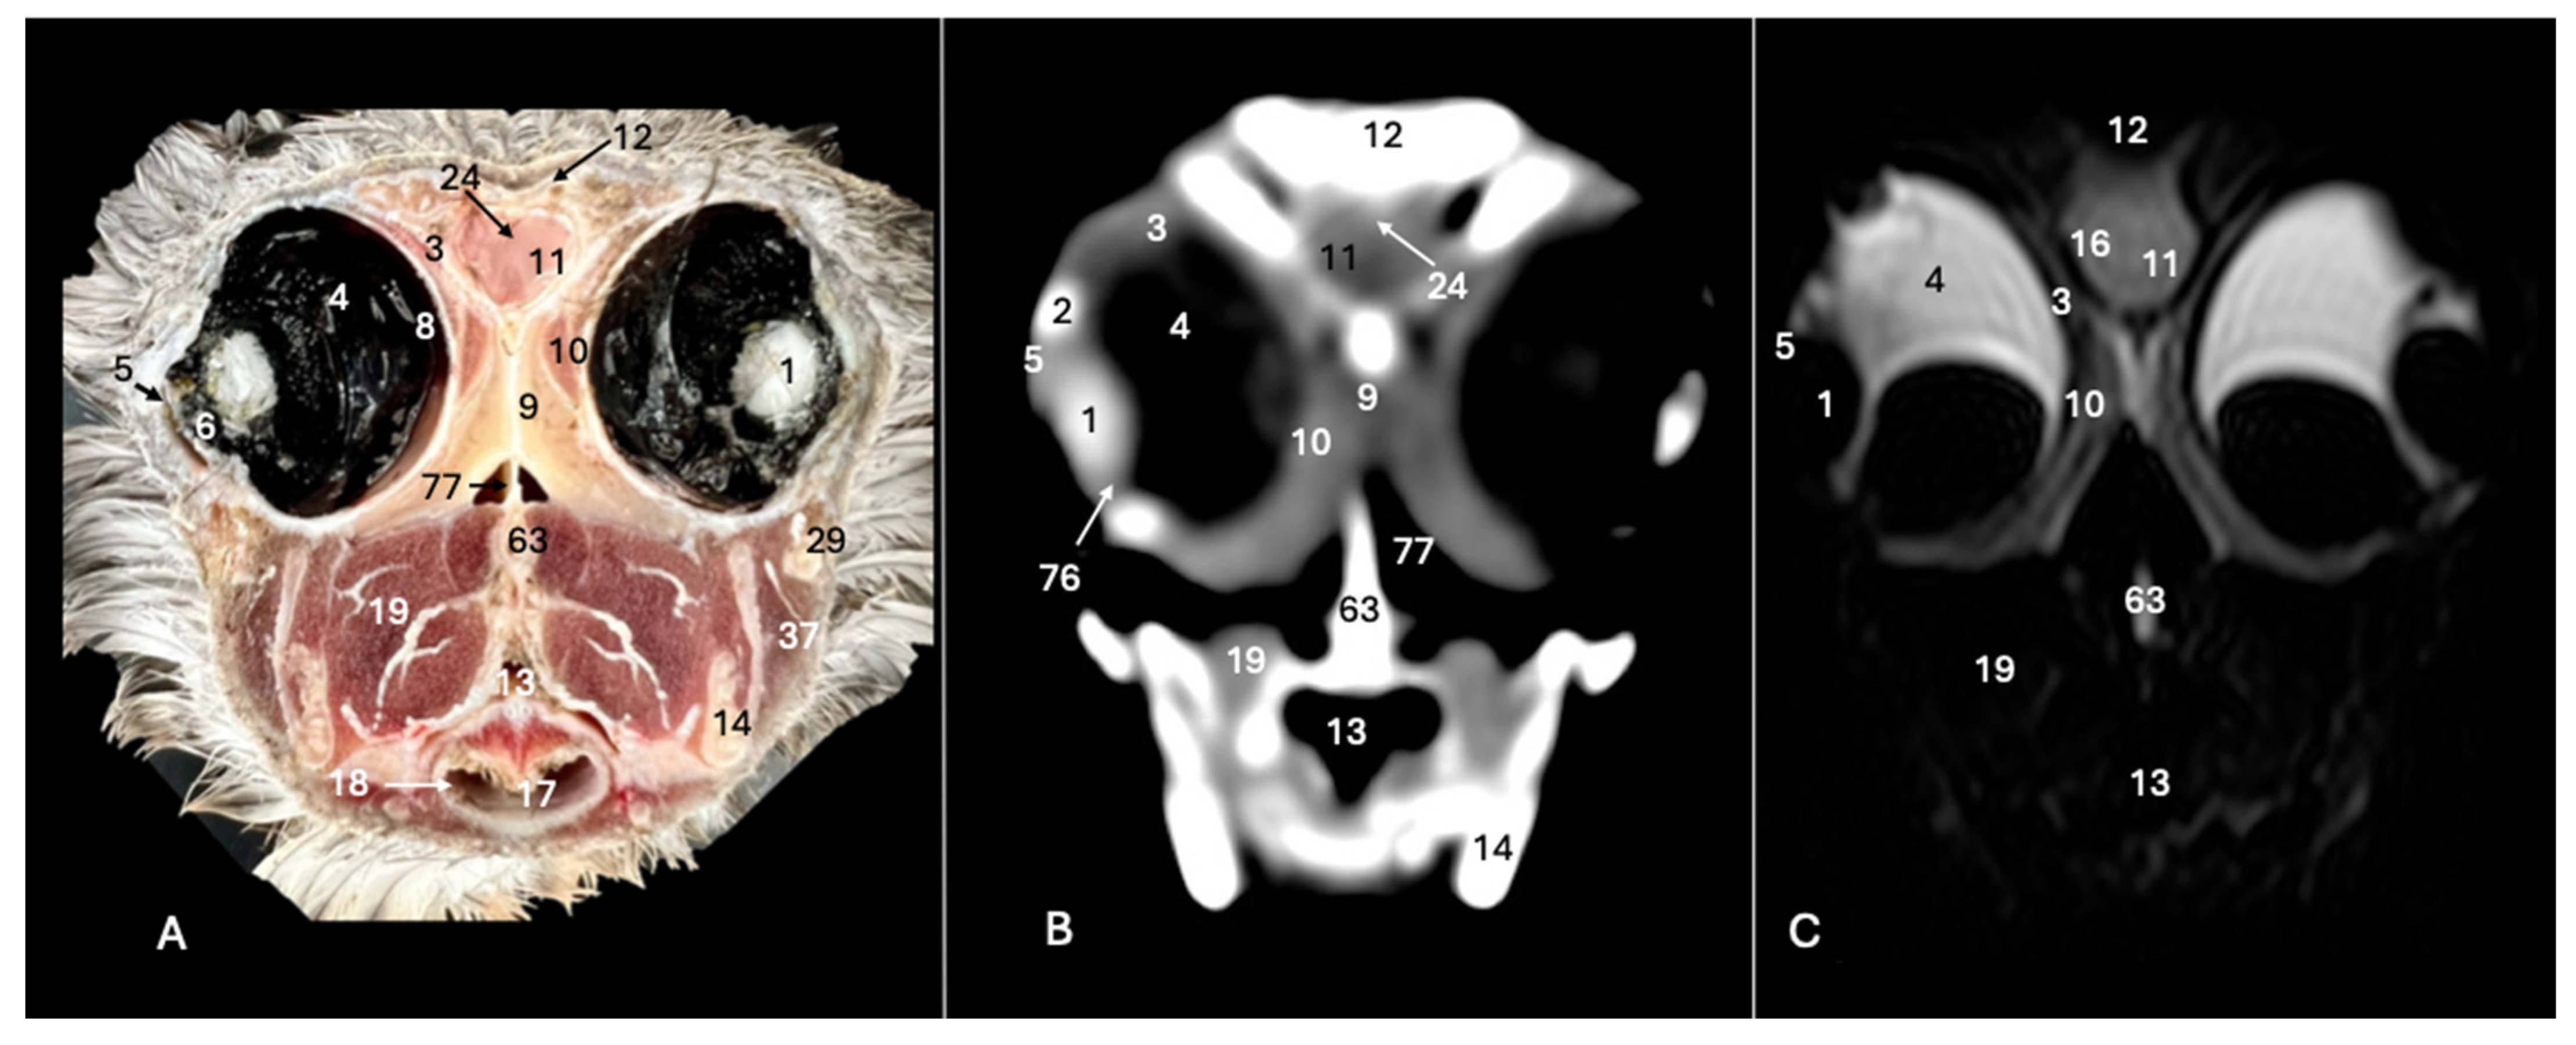

3. Result

3.1. Anatomical Sections

3.2. Computed Tomography (CT)

3.3. Magnetic Resonance Imaging (MRI)